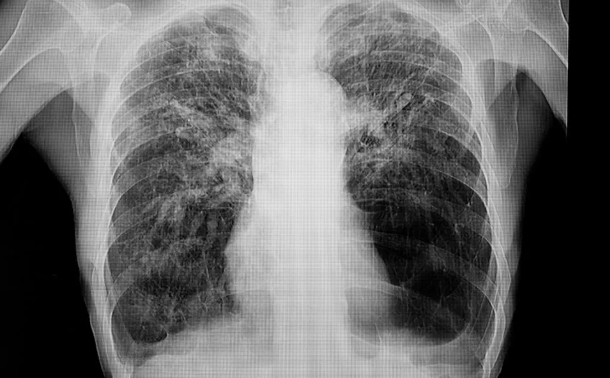

폐결절이 양성일 가능성은?

폐결절이 양성인지 악성인지 판단하는 데에는 여러 요소가 관여합니다. 폐결절 양성 여부는 주로 다음과 같은 기준을 중심으로 접근합니다.

- 석회화(흰 점처럼 보이는 부분)가 있으면 대부분 양성입니다.

- 결절이 오랜 기간 변화 없이 유지되면 양성으로 간주할 수 있습니다.

- 감염성 염증 후 생긴 반흔 또는 조직 변화도 폐결절로 보일 수 있습니다.